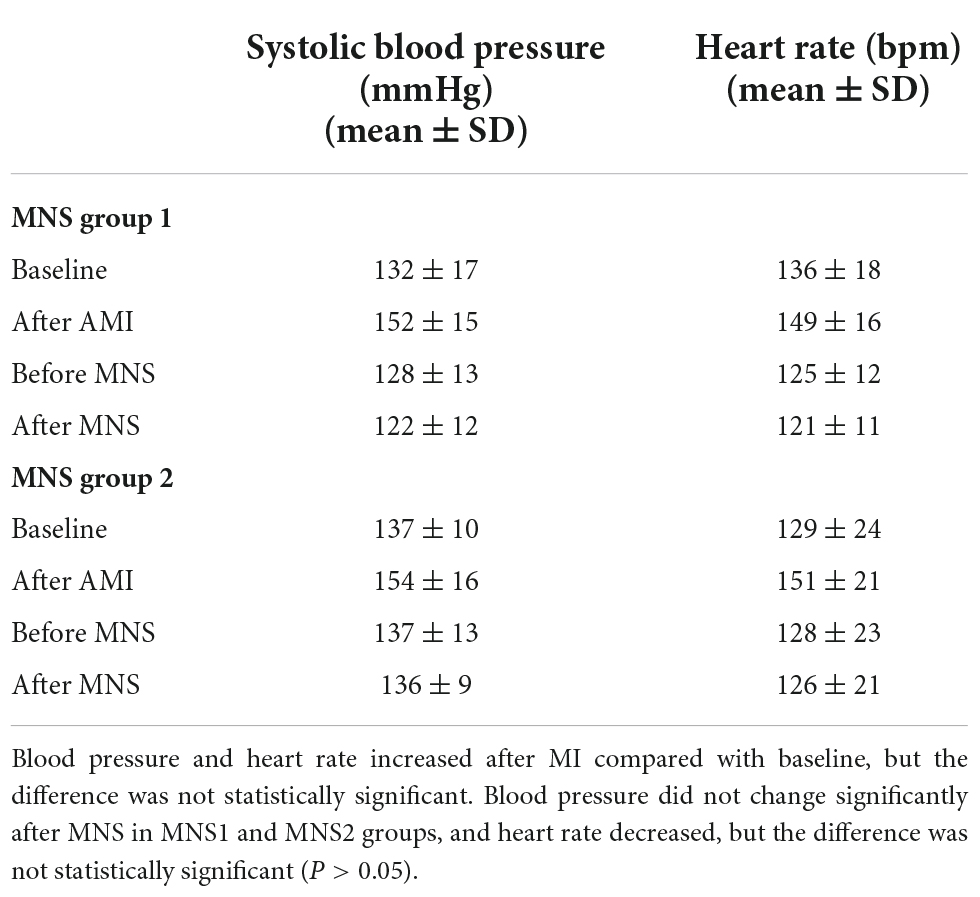

We performed successful experiments on 13 of 15 dogs with acute MI. Two dogs died during the rearing period. After 4 weeks, six dogs and seven dogs were assigned to MNS group 1 and MNS group 2, respectively. During MNS, the heart rate exhibited a decreasing trend in the MNS group 1 and MNS group 2, but this did not contribute to the significant difference. For instance, the heart rate was 125 ± 12 beats/min before MNS and 121 ± 11 beats/min after 30 min of MNS (P > 0.05) in the MNS group 1. The heart rate and blood pressure in the baseline, acute MI, and before and after 30 min of MNS are shown in Table 1 and Figure 4.

Table 1. Heart rate and blood pressure of experimental dogs in baseline, acute myocardial infarction (MI), and after 30 min of median nerve stimulation (MNS).

Figure 4. Representative graphs of blood pressure, heart rate, and electrocardiographic monitoring in the MNS1 group dog during baseline, acute myocardial infarction (MI), and before and after 30 min of MSN. MSN, median nerve stimulation.